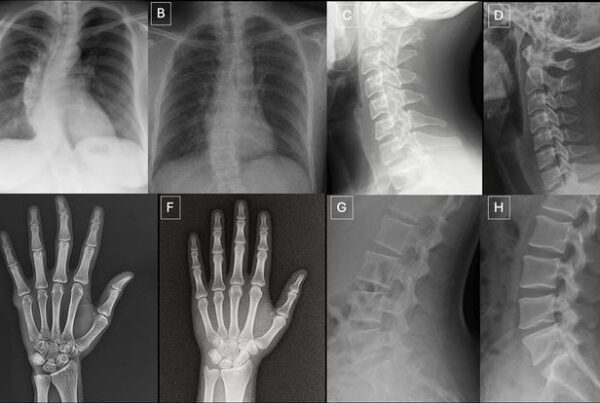

Embora os detalhes variem entre os estados, algumas temáticas recorrentes emergem nos projetos de lei que o ACR monitora. A transparência algorítmica é um pilar frequente: vários estados querem que pacientes sejam notificados quando ferramentas de IA participam da análise de seus exames de imagem. A lógica é que o paciente tem direito de saber se sua mamografia, tomografia ou radiografia foi interpretada com auxílio computacional.

Outro tema central é a supervisão médica obrigatória. A maioria dos projetos exige que um radiologista licenciado revise e aprove qualquer resultado gerado por IA antes que ele seja comunicado ao paciente ou incorporado ao prontuário. Essa exigência alinha-se com a posição histórica do ACR de que a IA deve funcionar como ferramenta de apoio ao radiologista, nunca como substituto.

Os dados recentes sobre o impacto da IA na prática radiológica são convincentes. Estudos demonstram que ferramentas de IA podem reduzir a carga de trabalho em mamografia em até 64%, enquanto algoritmos de detecção auxiliada por computador já são usados em larga escala para rastreamento de câncer de pulmão e análise de imagens cerebrais. A questão regulatória, portanto, não é se a IA será usada em radiologia — ela já é —, mas sob quais condições e com quais garantias.